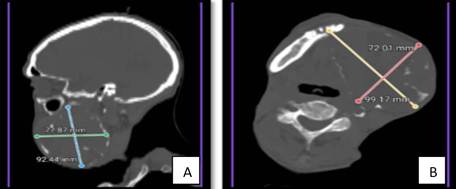

3. Estudio por Imágenes (Tomografía Axial Computarizada - TAC): La TAC facial reveló una lesión osteolítica, expansiva y multiloculada de márgenes bien definidos, que ocupaba por completo el cuerpo y la rama ascendente de la hemimandíbula izquierda, con dimensiones de 7.2 x 9.9 cm en el plano axial y 7.8 x 9.2 cm en el plano coronal (Figura 2A y 2B). No se evidenciaron adenopatías patológicas ni invasión de tejidos blandos adyacentes, pero sí una destrucción ósea que superaba el 50 % de la mandíbula.

Fig. 2: Cortes de TAC (A: sagital, B: axial) que muestran la lesión osteolítica multiloculada en mandíbula izquierda.